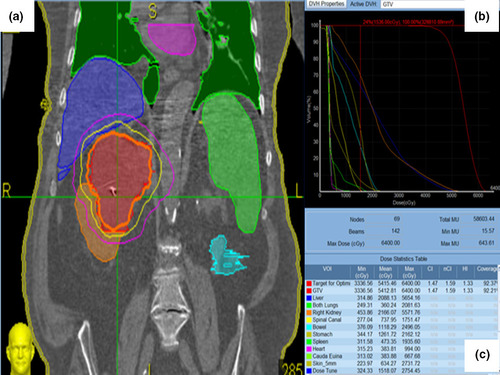

The computed tomography (CT) simulation images of 10 patients with unilateral RCC previously treated on a Phase 1 trial at Institution 1 were anonymized and shared with Institution 2 after IRB approval. Treatment planning was generated through five different platforms aiming a total dose of 48 Gy in three fractions. These platforms included: Cyberknife and volumetric modulated arc therapy (VMAT) at institution 1, and Cyberknife, VMAT, and pencil beam scanning (PBS) Proton Therapy at institution 2. Dose constraints were based on the Phase 1 approved trial.

Compared to Cyberknife, VMAT and PBS plans provided overall an equivalent or superior coverage to the target volume, while limiting dose to the remaining kidney, contralateral kidney, liver, spinal cord, and bowel.